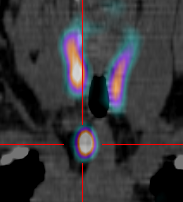

La scintigraphie parathyroïdienne est un examen qui reflète le fonctionnement des glandes parathyroïdes.

Celles-ci sont au nombre de quatre et le plus souvent situées en arrière de la thyroïde mais parfois plus bas, dans le thorax.

Dans certains cas, l'hyperfonctionnement d'une ou plusieurs d'entre-elle(s) peut être responsable d'un dérèglement hormonal nécessitant une opération.

L'examen a pour but de localiser précisément l'anomalie et de faciliter la prise en charge chirurgicale.